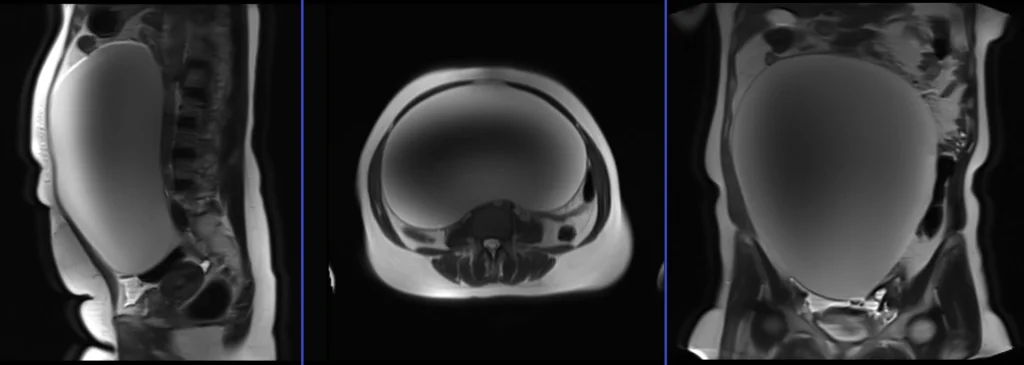

MRI localiser

A three-plane localiser must be taken at the beginning to localise and plan the sequences. Localisers are normally less than 25 seconds and are T2-weighted low-resolution scans.